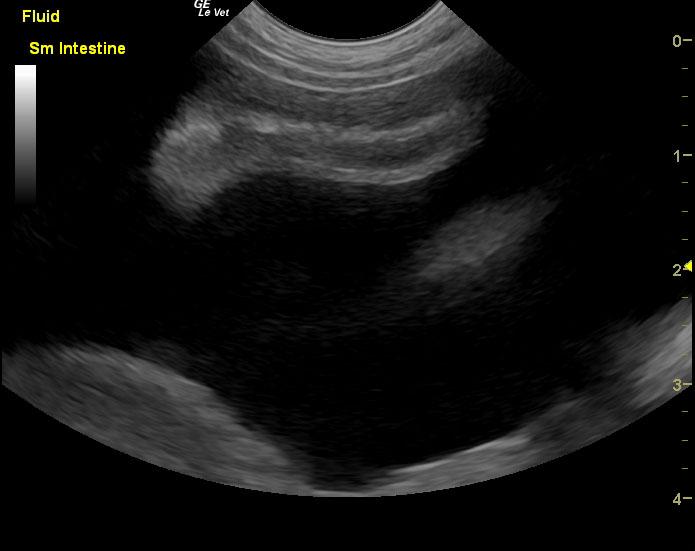

Protein losing enteropathy.

Lymphangectasia type presentation with secondary ascites.

If the ascites is transudate based on abdominocentesis this would be most consistent with protein losing enteropathy and secondary albumin loss, but given that the bloodwork was taken 4 days prior to the sonogram my concern is that the albumin is likely lower than 1.7 at this point. Anything less than 1.5 would justify poor oncotic pressure and free fluid formation. Urinalysis and assessment for concurrent protein losing nephropathy would be recommended. Liver function may also be compromised adding to the albumin loss issue. Plasma transfusion, broad spectrum deworming, calcium supplementation, Purina HA or Royal Canin HP diet, Metronidazole and Prednisone therapy would all be indicated. However, corn oil testing and endoscopy would be ideal for a definitive diagnosis as well as mucosal, gastric and duodenal biopsies.